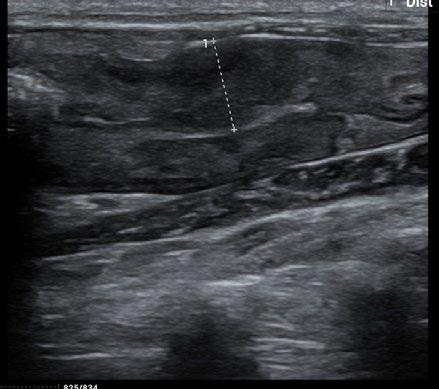

The owners came to us for a second opinion. Our ultrasound confirmed the findings of the previous clinic. There was a marked focal thickening of the descending colon:

Figure 2. Ultrasound image of the caudal abdomen showing marked thickening (10.9 mm) of the descending colon

Although neoplasia was indeed considered in the differential diagnosis, a recent publication (Müller et al JFMS 2023—Abdominal ultrasonographic findings of cats with feline infectious peritonitis—an update) had also indicated that this was amongst the increasingly varied recognised presentations for FIP. Indeed, historically it was referred to as ‘focal FIP’.